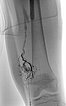

In the same session, sclerotherapy is performed using the direct puncture technique. Under ultrasound guidance, the venous malformation is punctured and contrast medium is injected.

A draining vein was immediately contrasted, which drains into the femoral vein and thus communicates with the deep conducting venous system. This communication was occluded with ethanol gel.

After occlusion of the drainage, complete sclerotherapy of the VM was possible because the liquid sclerosing agent could no longer drain off via the communicating vein.